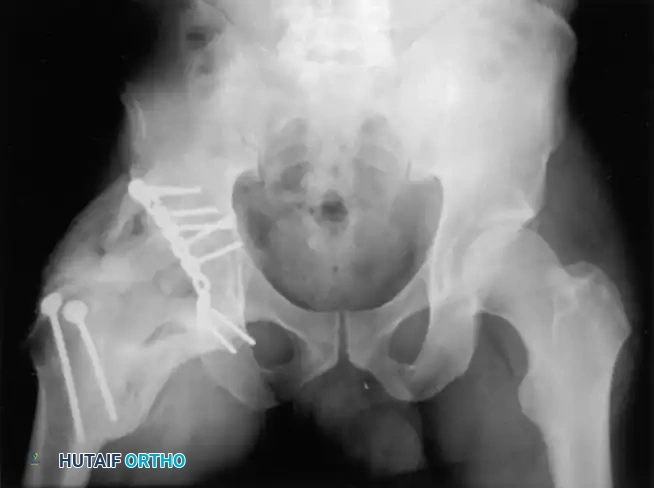

Standard Pelvic Radiography and Judet Views

The initial evaluation begins with an Anteroposterior (AP) view of the pelvis. This view assesses the six fundamental radiographic landmarks of the acetabulum:

1. Iliopectineal line (Anterior column)

2. Ilioischial line (Posterior column)

3. Radiographic teardrop (Medial wall)

4. Acetabular roof (Weight-bearing dome)

5. Anterior lip of the acetabulum

6. Posterior lip of the acetabulum

To fully conceptualize the fracture in three dimensions, the 45-degree oblique views described by Judet are mandatory:

* Iliac Oblique View: The patient is rolled 45 degrees toward the uninjured side. This view profiles the posterior column and the anterior wall of the acetabulum.

* Obturator Oblique View: The patient is rolled 45 degrees toward the injured side. This view profiles the anterior column and the posterior wall of the acetabulum.

Associated Surgical & Radiographic Imaging

Hutaifortho's Orthopaedic Diagram